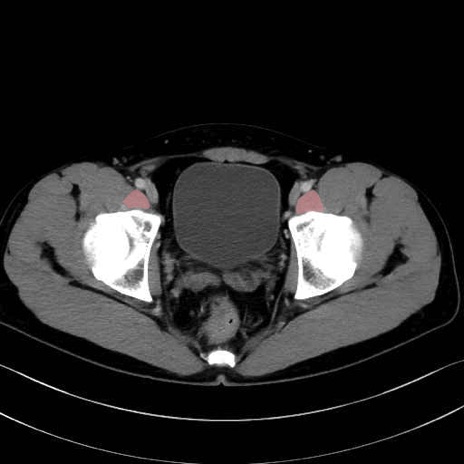

4. 深層外旋六筋(股関節の深部)

梨状筋 (Piriformis)

内閉鎖筋 (Obturator internus)